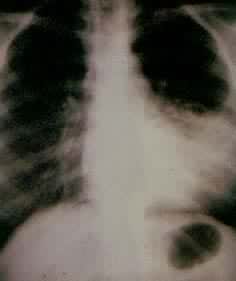

全身性疾病的肺部表现心源性肺水肿可发生于各种原因引起的左心衰竭。创伤休克、严重感染可引起弥漫性肺毛细血管的损伤而致肺间质、肺泡水肿,表现为成人呼吸窘迫综合征。低蛋白血症(如肝硬变、肾病综合征等)可致胸腔积液(漏出液),急性胰腺炎患者也可发生胸腔积液和肺部弥散性病变。结缔组织病、淋巴瘤、恶性组织细胞病、白血病、风湿病等均可有肺部或胸腔积液的表现。